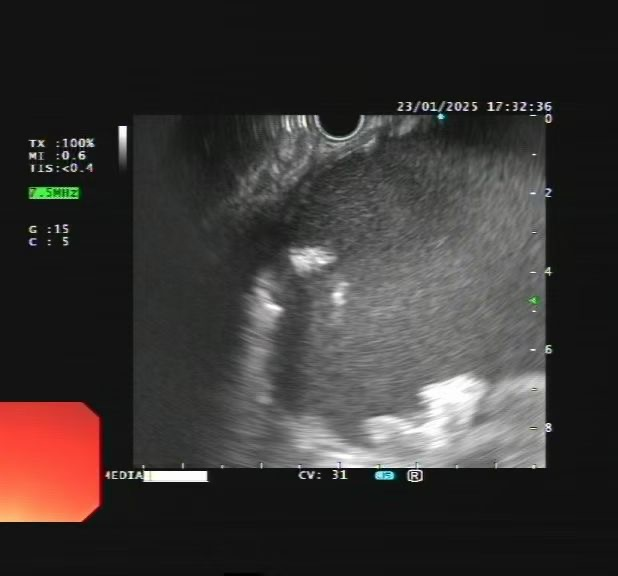

针对张奶奶的病情,科室立即联系普外二科、重症医学科、介入室等学科召开多学科会诊。综合会诊意见,消化内科主任孙志宏带领消化内科团队进行病例讨论,经过详细讨论及超声内镜检查,确诊该囊性病变为胰腺包裹性坏死。

在与患者及家属充分沟通后为其实施“超声内镜引导下胰腺包裹性坏死穿刺引流术+支架置入术”,术中,支架顺利释放,大量褐色囊液涌入胃内。术后复查显示,囊腔明显缩小。